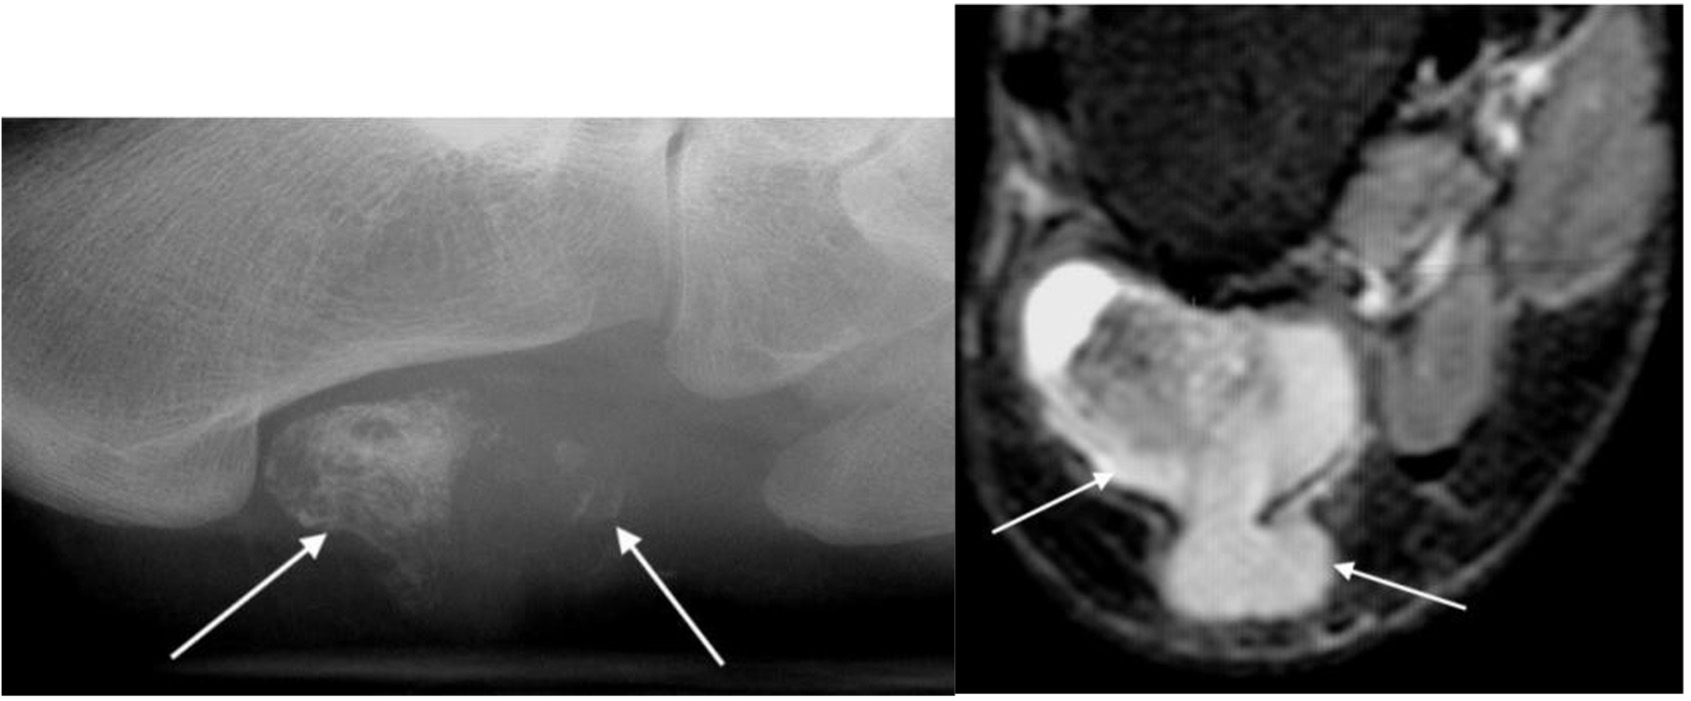

Figure 1. Xray and MRI of synovial sarcoma

Synovial sarcoma

- young to middle aged

- intralesional calcifications in soft tissue mass

- radical surgical excision with wide margins

- 5-year survival ~55%